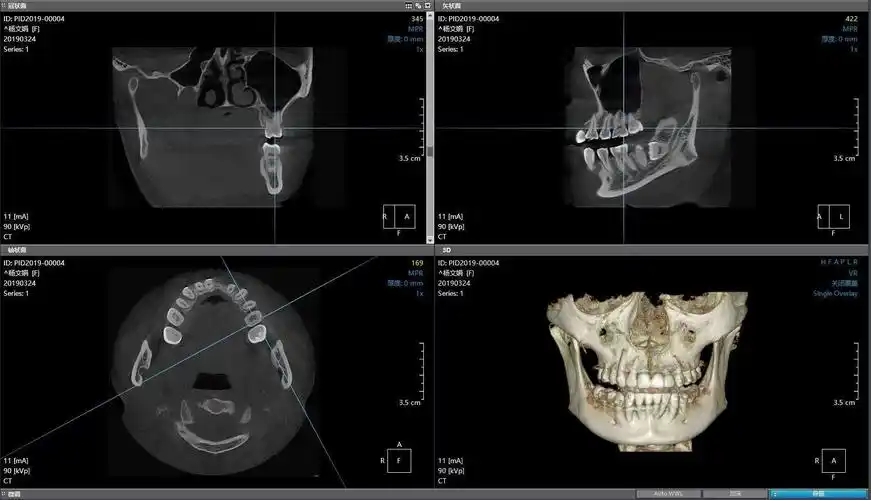

镇安县中医医院口腔ct率先开机啦!

四川大学华西医院龙泉医院超大视野口腔ct投入使用